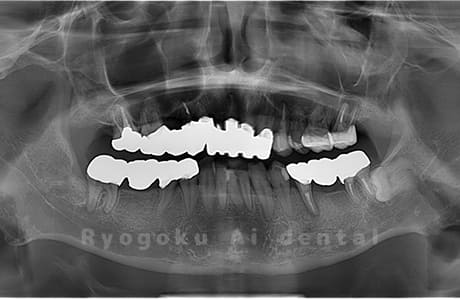

Case01

- 原因

- 水平埋伏智歯

- 治療内容

- 下顎の水平埋伏智歯を抜歯

<リスク・副作用>

手術後は痛み、腫れ、痺れなどの副作用が生じる場合があります。